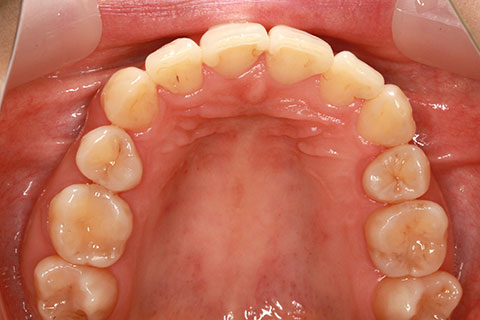

治療中(開始半年後)

- 年齢・性別

- 25歳女性

- 治療期間

- 2年0ヶ月

- 抜歯

- 上下4番抜歯

- 治療費

- 110万円

- 治療内容

- 施術の副作用(リスク)

- 表側矯正と比較して、力学的な操作性が複雑なため、ボーイングエフェクトを起こしやすい。